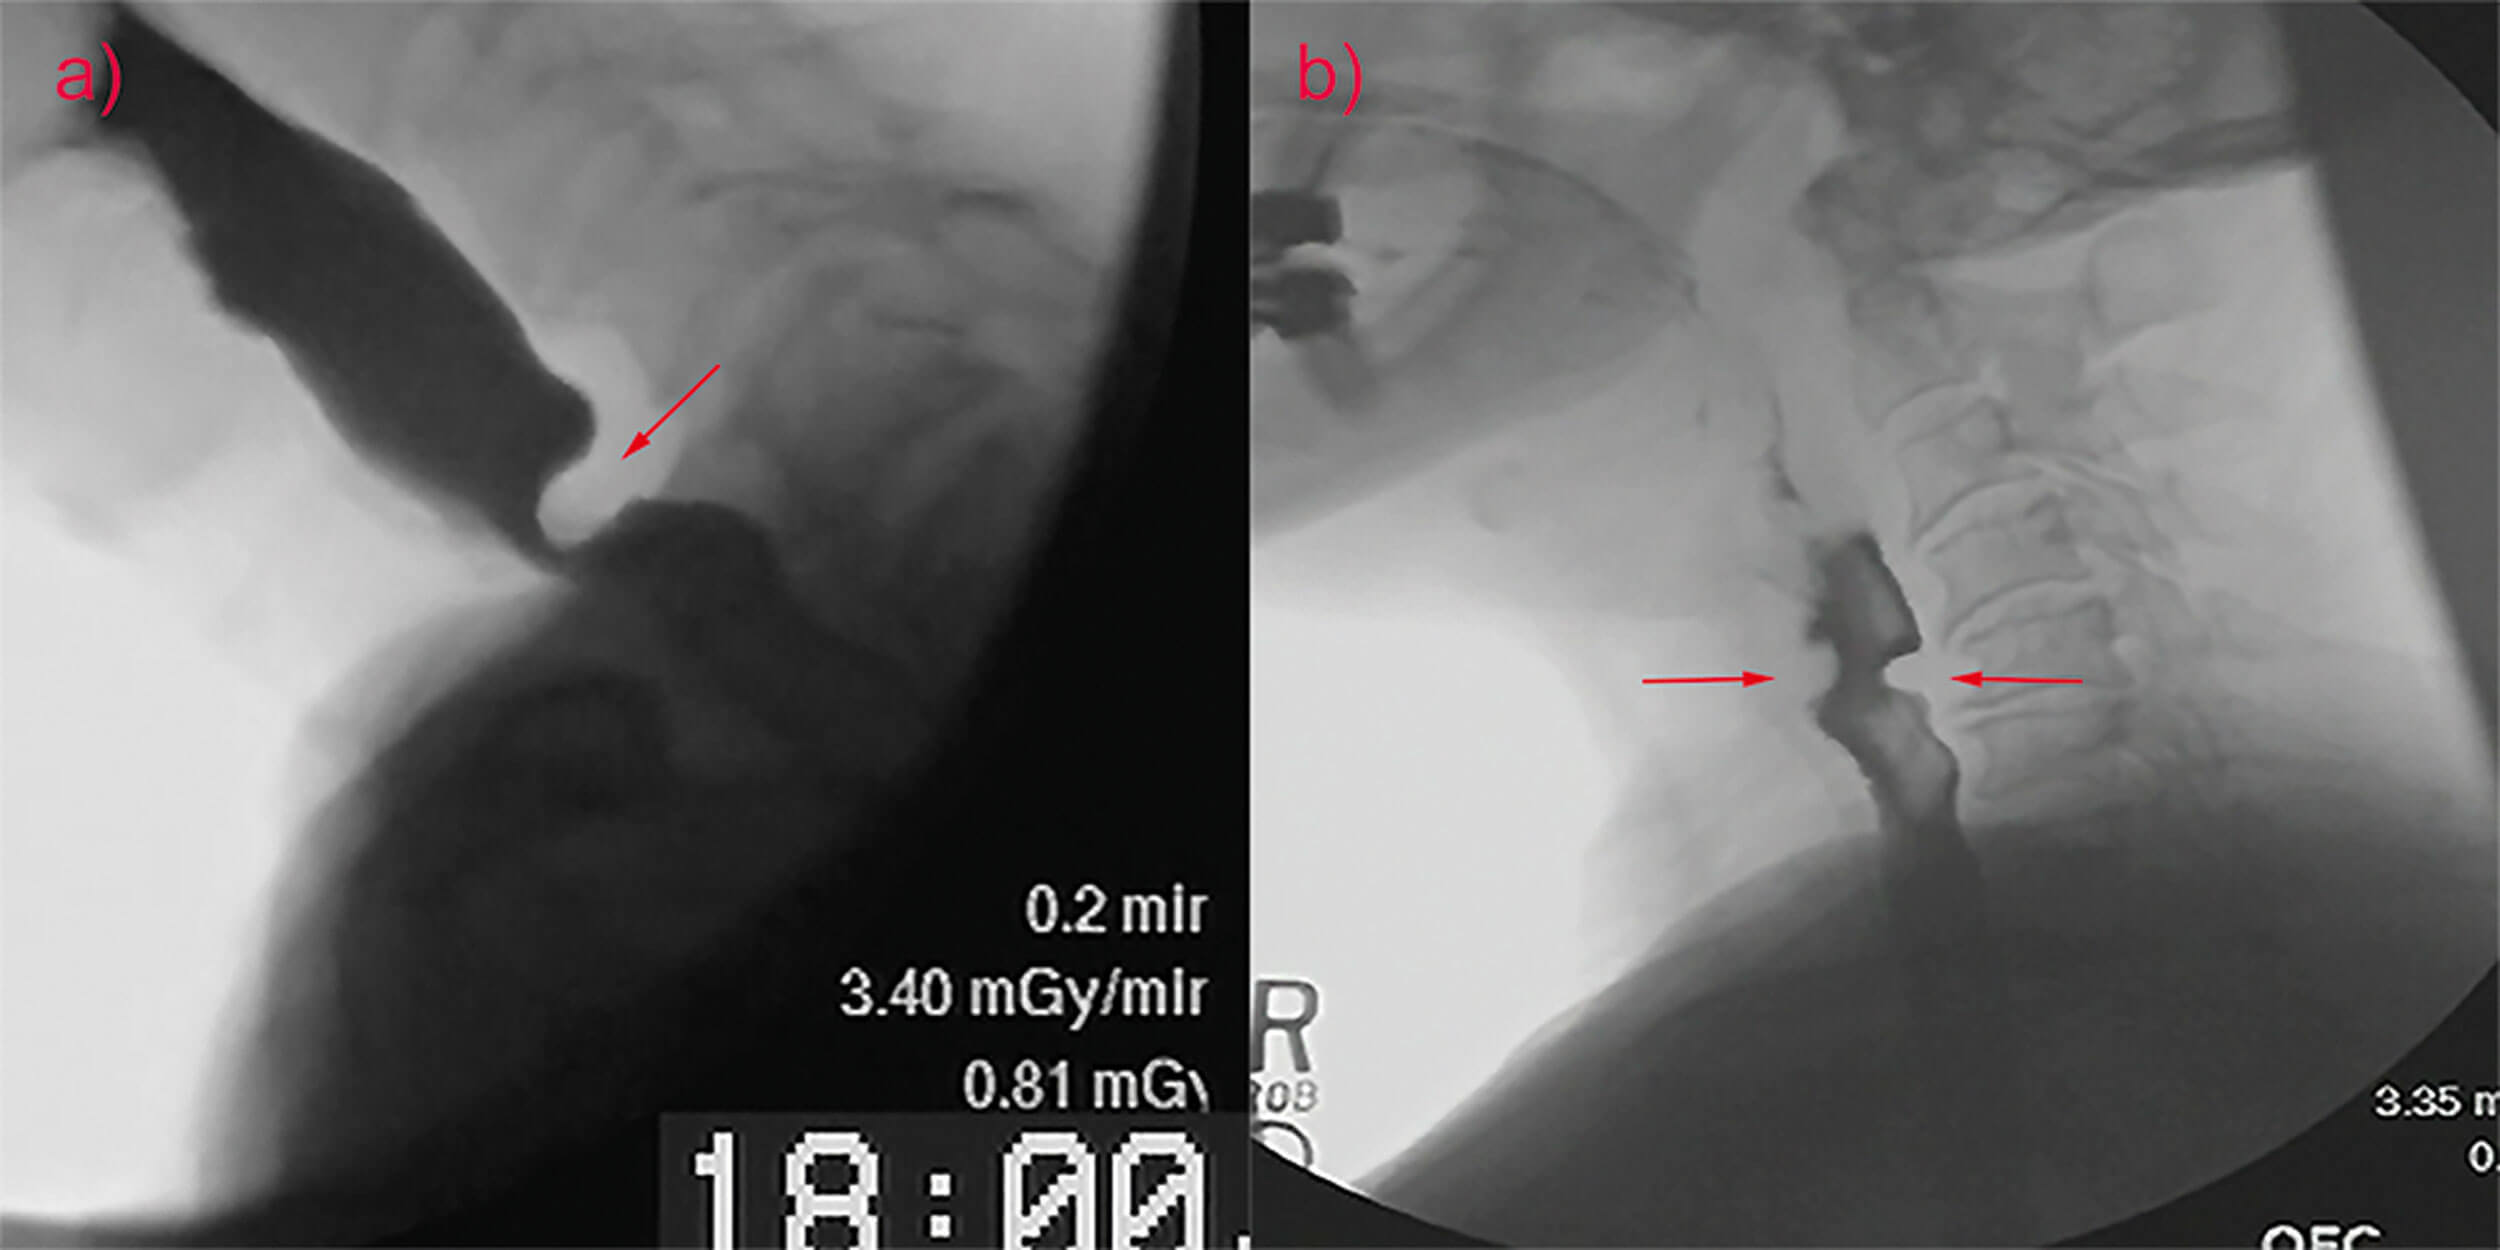

The lower position of the larynx in the neck negatively impacts opening of the upper oesophageal sphincter. Other factors that diminish upper oesophageal sphincter opening with advancing age include a 30% prevalence of cricopharyngeus muscle ‘bars’ in normal individuals >60 years of age and over a 60% prevalence of cricopharyngeal webs in elderly cadavers (Figure 1).

Figure 1. Cricopharyngeus muscle bar (a) and cricopharyngeal web (b).

The high prevalence of cricopharyngeal webs in the elderly is hypothesised to be secondary to the repeated mechanical trauma of the cricoid against the cervical spine that occurs over a lifetime of swallowing. The increased prevalence of cervical osteophytes with age contributes to this trauma and causes a further reduction in upper oesophageal sphincter opening. Although the hyoid bone attempts to compensate for this reduced opening with greater and prolonged elevation, these efforts fall short.